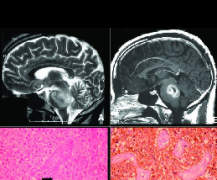

在磁共振成像脑,弥漫性脑干胶质瘤的特点是T1强度降低,异源T2增加。局灶性脑干神经胶质瘤的特征是T1为等信号至低信号至灰质,T2为高信号至灰质。 脑...

儿童脑桥弥漫内生型胶质瘤影像学特征, 儿童DIPGS的典型MRI表现为T1低信号和T2高信号。大多数还可以发现,由于脑桥增大,基底动脉受压或移位;增强后,...

组织和分子病理学特征。 近十年来,组织活检逐渐应用于DIPGS的诊断。以往认为DIPGS立体定向活检是不必要的。在大多数情况下,仅靠临床表现和MRI检查结...